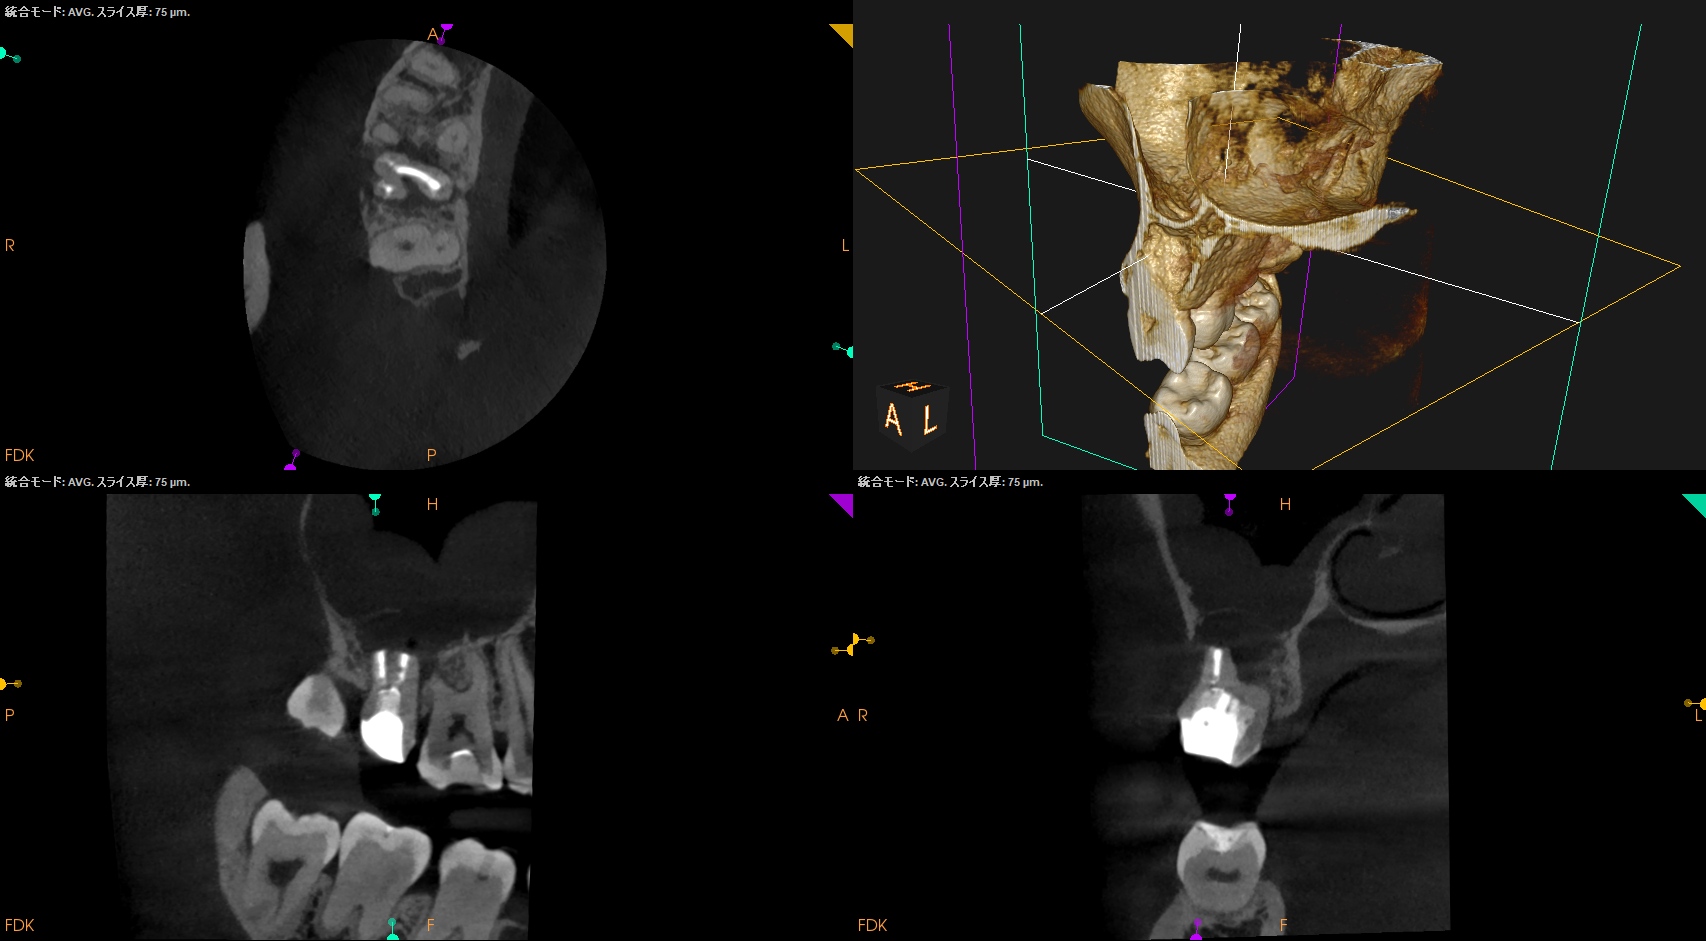

CBCT(2025.11.11)

MB

DB

P

根管は石灰化&すでに拡大済みであるので、再根管治療ではなく外科治療、つまり、Intentional Replantationの適応症である。